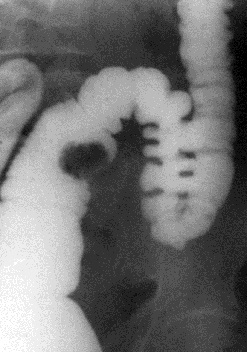

Нередко при исследовании пищеварительного канала можно выявить ограниченное уменьшение тени органа. Этот симптом называется также «дефект наполнения». В основе его чаще лежит опухолевый узел (рис 16, рис. 17), конкремент (рис. 18), который, заполняя часть полости органа, не дают проникать туда контрастной массе. Кроме этого, этот симптом может быть обусловлен наличием инородного тела неметаллической плотности. Дефект наполнения по локализации по отношению к просвету органа разделяется на 1) центральный; 2) краевой; 3) циркулярный.

Рис. 17. Прицельная ирригограма в условиях тугого наполнения. В сигмовидной кишке определяется краевой дефект наполнения больших размеров. Опухоль